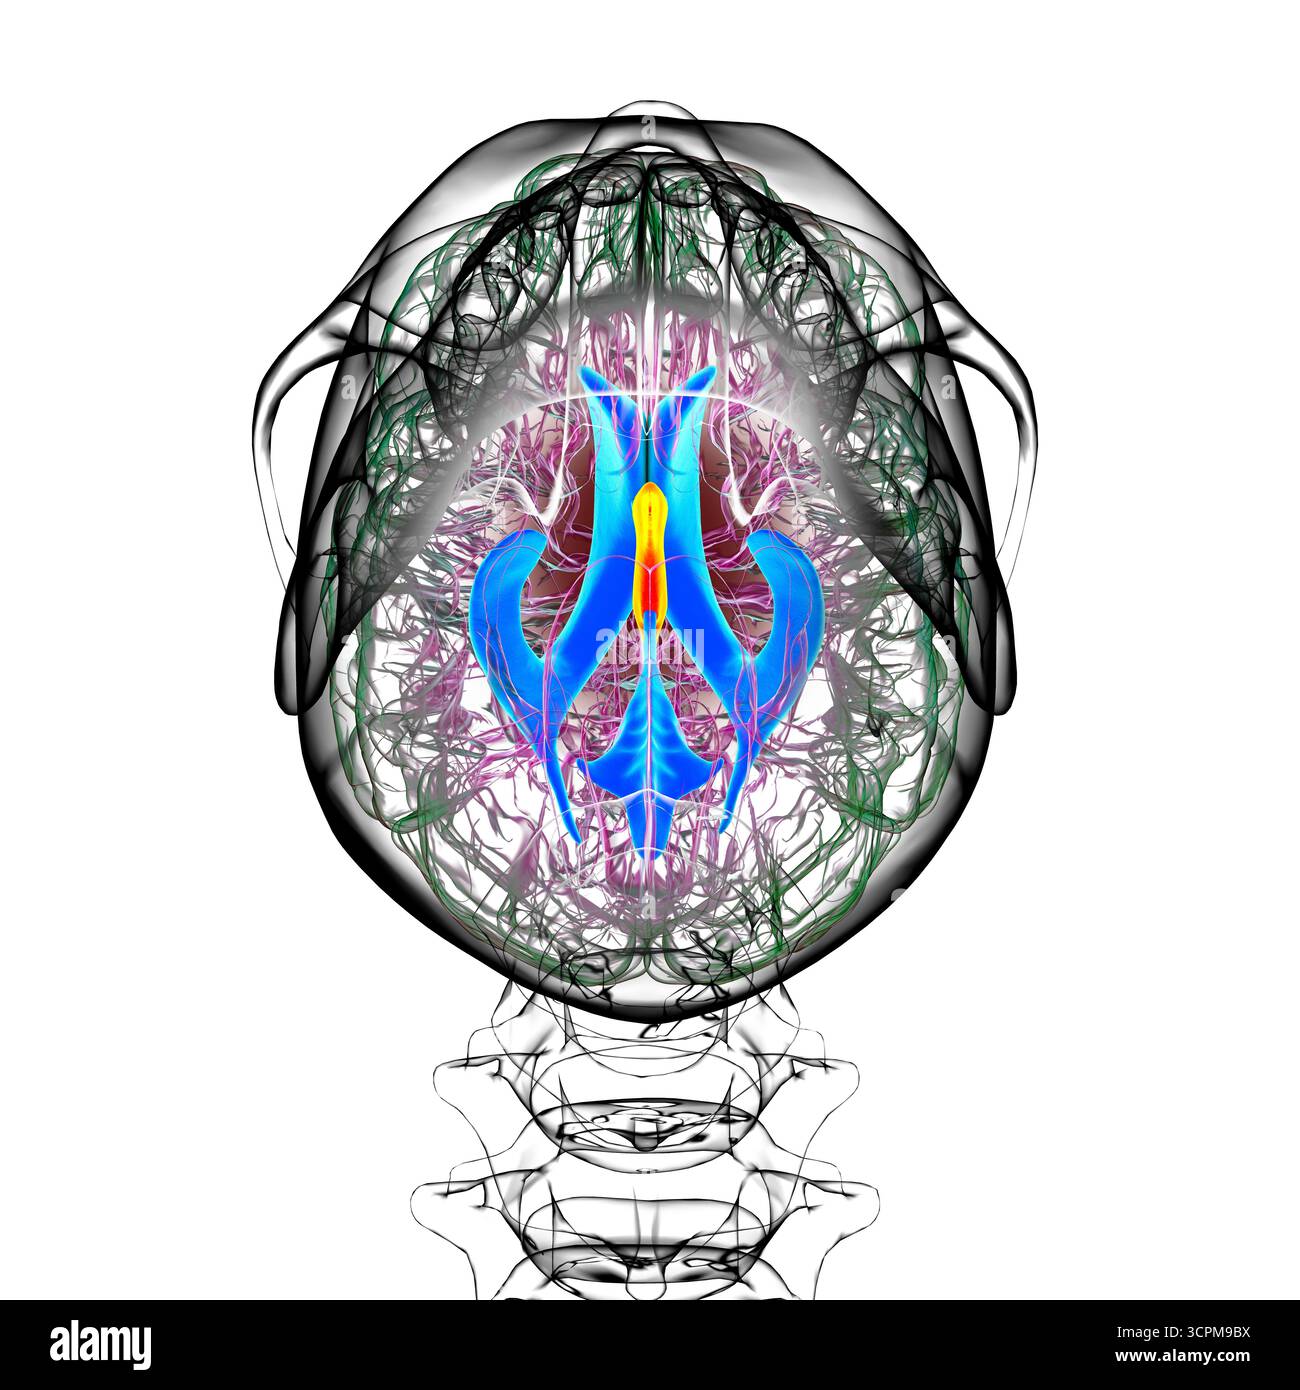

RF3CPM9BH–Illustration des dritten Hirnventrikels, einer lebenswichtigen Komponente des Hirnventrikulärsystems.

RF3CPM9BX–Illustration des dritten Hirnventrikels, einer lebenswichtigen Komponente des Hirnventrikulärsystems.

RF3CPM9C1–Illustration des dritten Hirnventrikels, einer lebenswichtigen Komponente des Hirnventrikulärsystems.